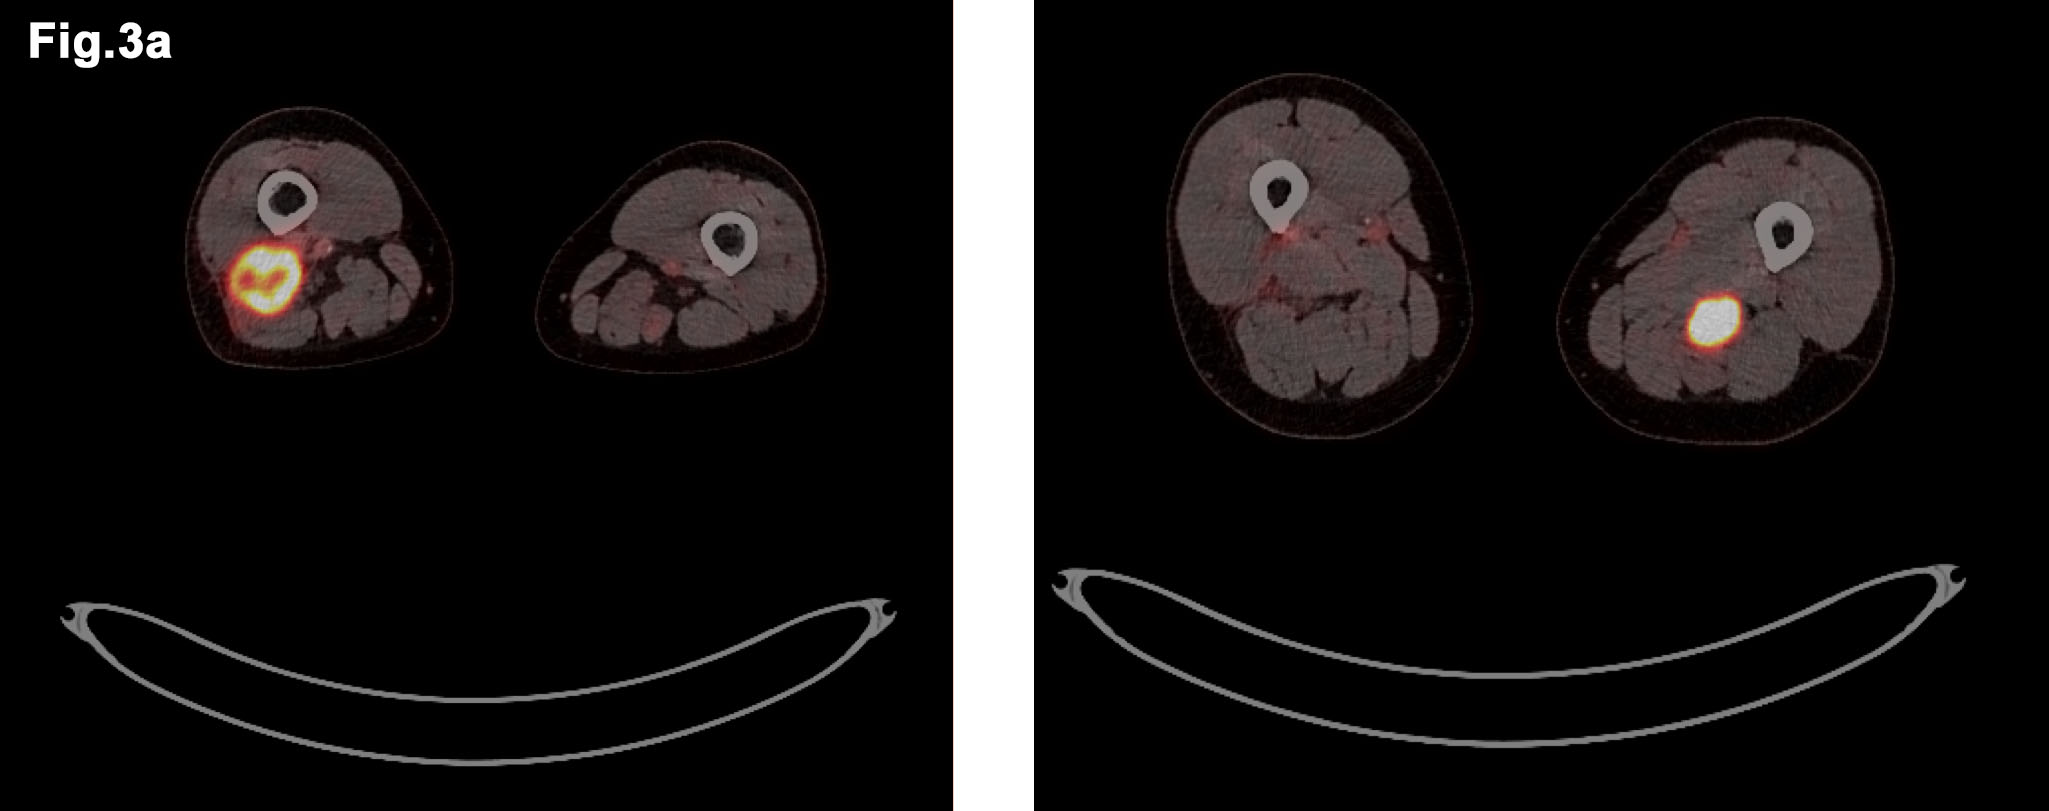

Figure 3 – PETCT images demonstrate avid lesions in both thighs (a) and further avid lesion in posterior mediastinum (b) - PET CT images of both legs demonstrate avid FDG take up in right and left lesions (Fig 3a) - ET CT showing Mediastinal primary tumour which also demonstrates FDG avidity (Fig 3b)

- PET/CT Sep 2016 (Figure 3)

- FDG acid lesions seen in both thighs and within posterior mediastinum